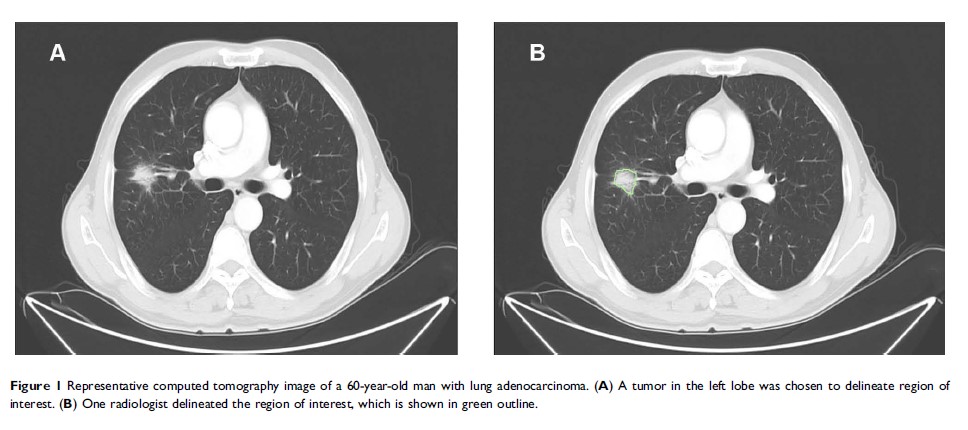

计算机断层扫描组织学特征在接受立体定向放射疗法的早期非小细胞肺癌患者中的预后作用